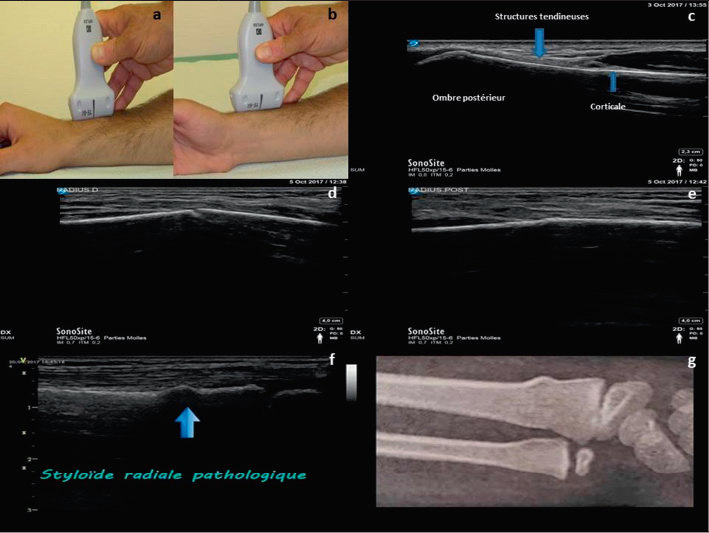

L Echographie Comme Prolongement De L Examen Clinique Du Praticien Revue Medicale Suisse